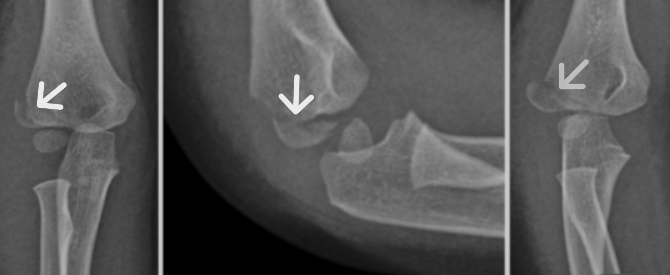

♦ 진단: X-ray,CT,MRI 등 영상의학적 검사를 통해 골절의 위치, 형태, 전위 여부, 성장판 침범 여부 등을 확인합니다. 소아의 뼈는 연골 부위가 많아 성인보다 진단이 어려운 경우가 있습니다.

상완골 외과 골절 : 팔꿈치 바깥쪽(외측과) 골절, 팔을 펴고 넘어질 때 발생, 성장판 손상 위험